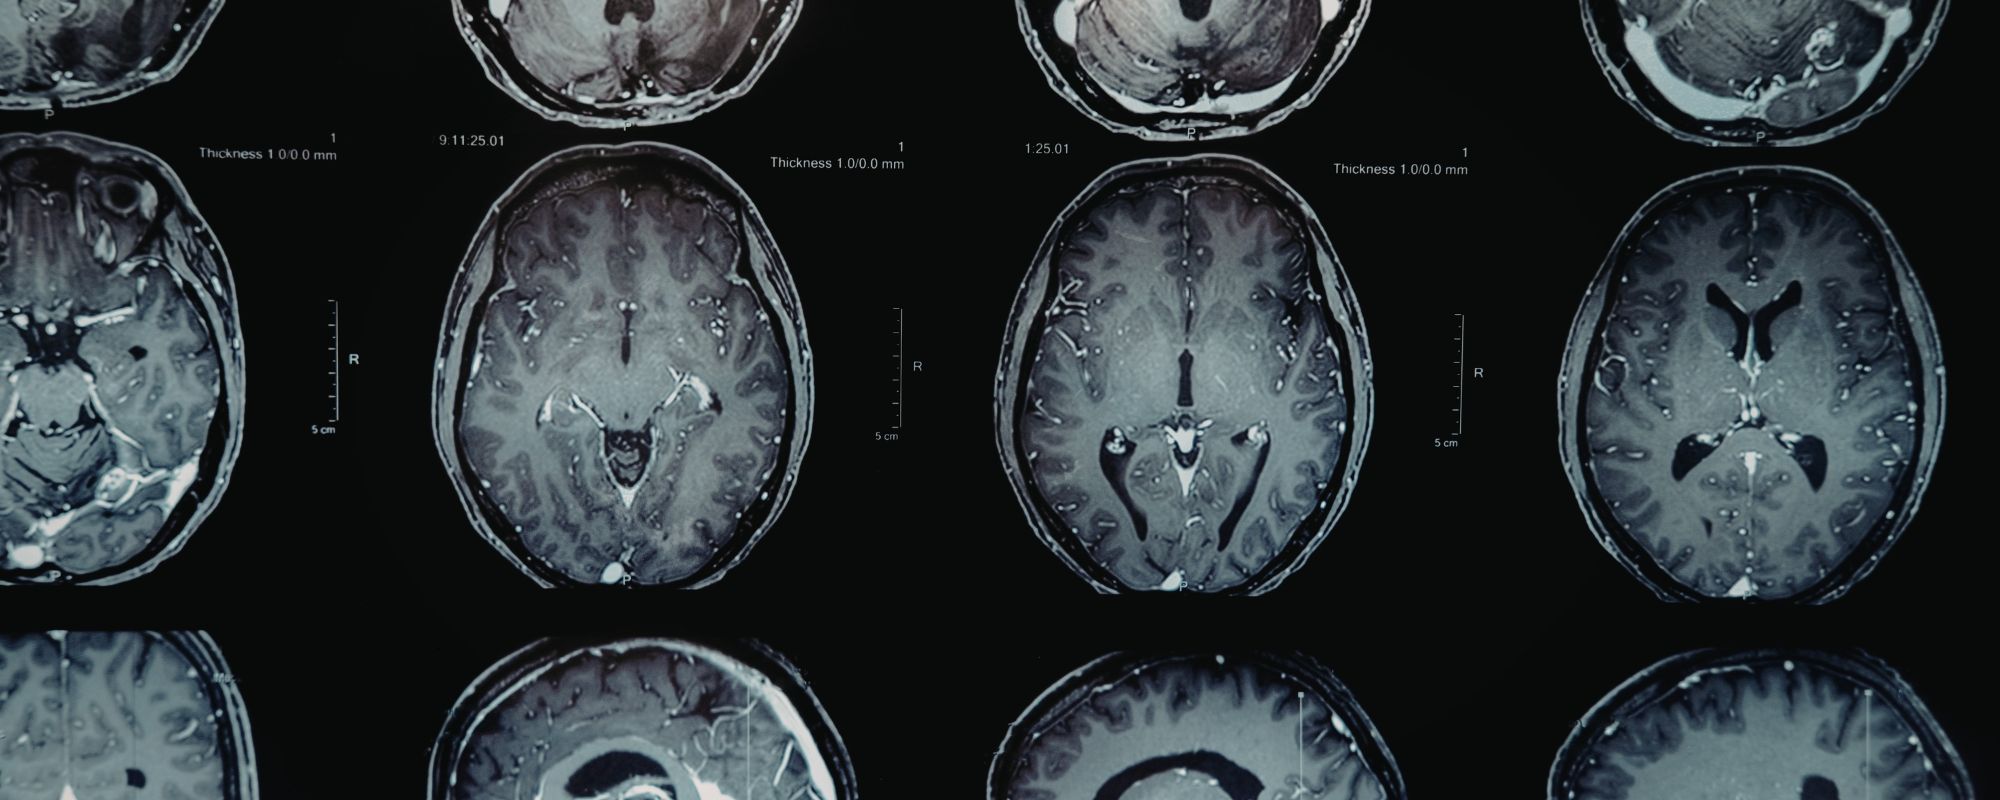

How oxycodone works is by acting by binding to specific receptors in the brain and spinal cord, altering the body’s perception of pain. While it is a valuable medicine for pain relief, especially in conditions such as cancer-related pain, oxycodone carries a high potential for addiction and is commonly abused.

The crux of its addictive potential lies in the way it interacts with the central nervous system. Like other opioids, oxycodone binds to specific proteins. These proteins, called opioid receptors, appear on nerve cells in the brain, spinal cord, gastrointestinal tract, and other organs.

When oxycodone attaches to these receptors, it can produce a sense of euphoria or intense pleasure by triggering the release of dopamine, a neurotransmitter associated with the reward pathways in the brain. The brain produces less dopamine naturally and quickly comes to depend on ever-increasing doses of oxycodone to feel dopamine.